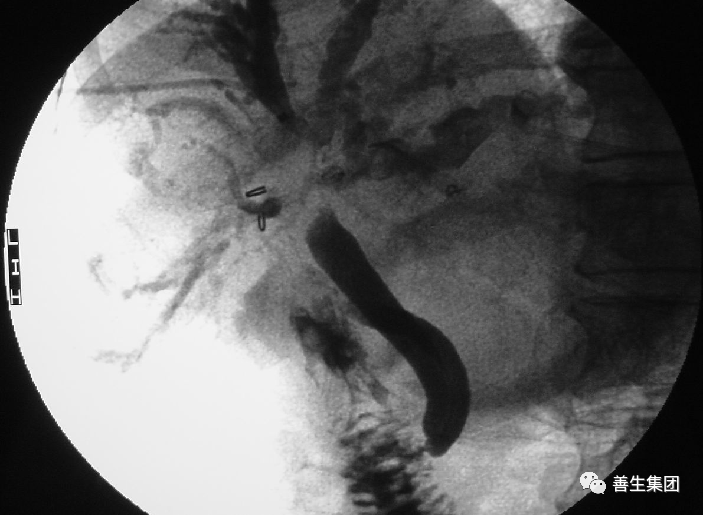

PTC示左右肝管内间广泛充盈缺损,为胆道出血正像